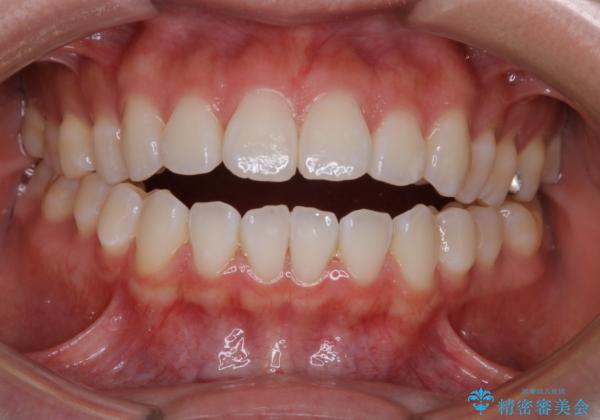

前歯で噛めない:オープンバイト(開咬)を非抜歯インビザラインで治療

- 上下の歯が噛んでいないことを気にしてご相談にいらした方です。

舌癖も認められたため、舌のトレーニングも併せて行い、矯正治療の効率化を図ると同時に後戻りのリスクを最小限に抑えるようにしました。

オープンバイトの方への治療は、通常抜歯を行いワイヤーによる矯正治療を行うことが多いですが、今回はインビザラインの特性を生かし、非抜歯にて綺麗な歯並びを作ることが出来ました。